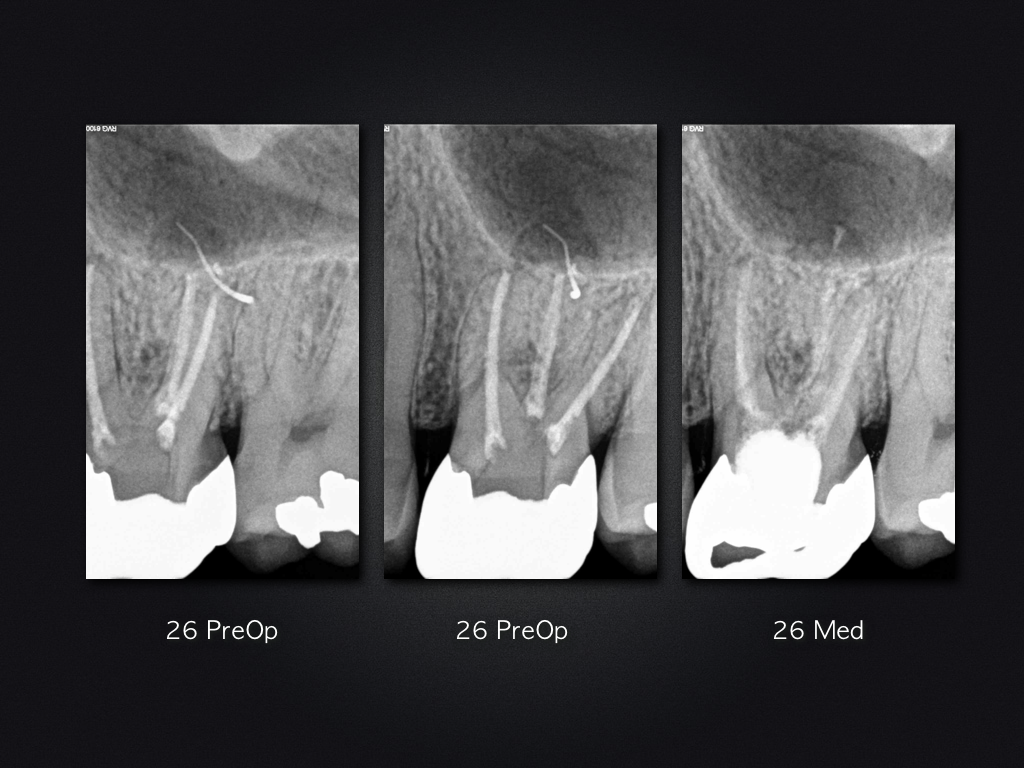

2D vs. 3D (XXV)